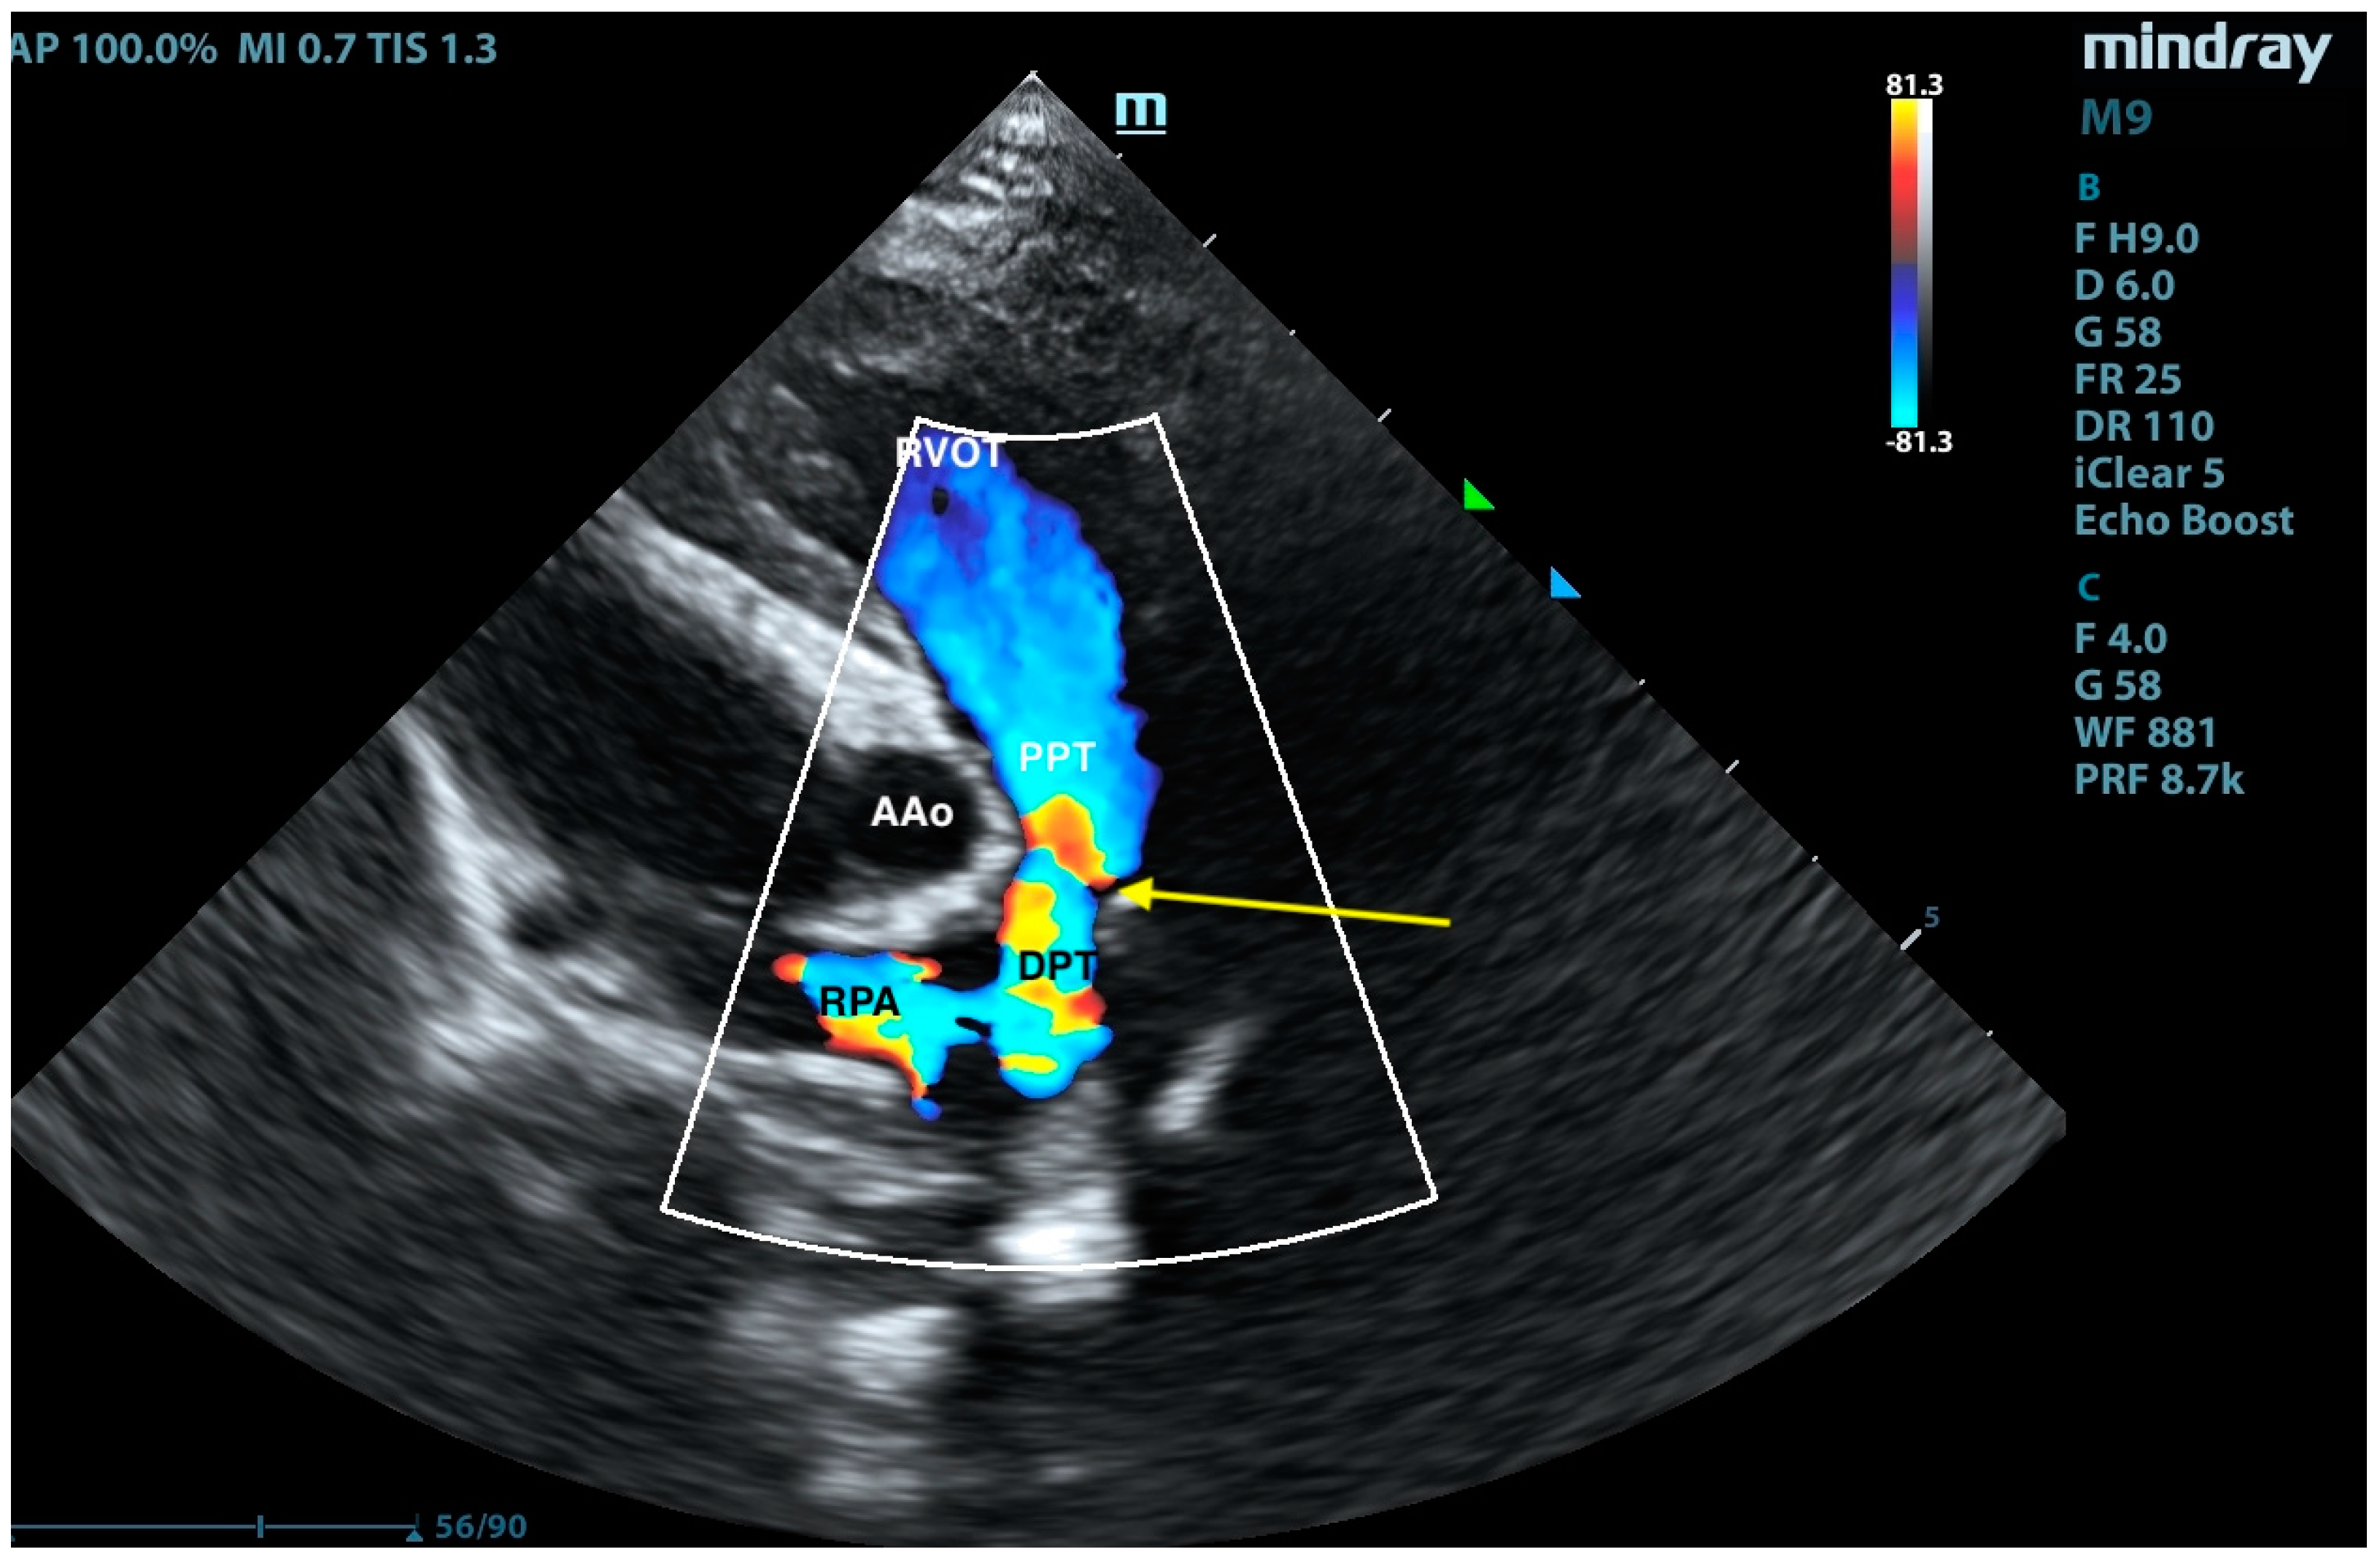

2. Case Presentation